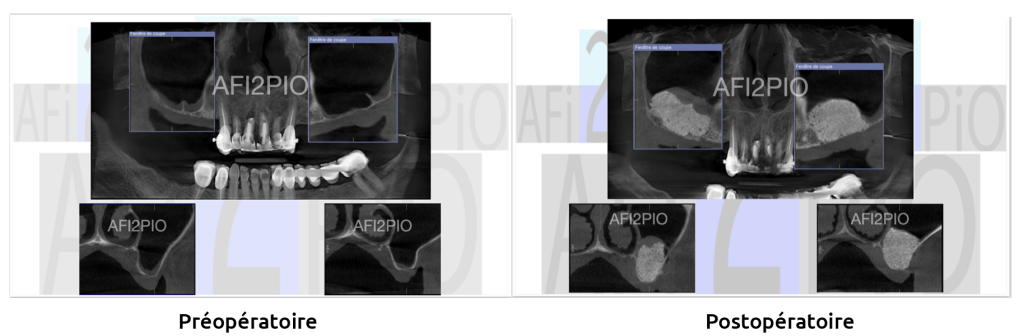

Docteur Laurent OHAYON : Techniques chirurgicales d’augmentation de la hauteur osseuse sous sinusiennes

Les différentes techniques d’augmentation de la hauteur osseuse sous sinusienne